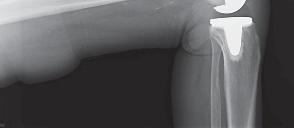

2. التصوير بالأشعة السينية (X-ray):

تُعد الأشعة السينية هي الأداة التشخيصية الأساسية لتقييم خشونة الركبة. يلتقط الأستاذ الدكتور هطيف صورًا للركبة من زوايا مختلفة، بما في ذلك صور الوقوف (Weight-bearing X-rays)، والتي تُظهر المفصل تحت تأثير وزن الجسم الطبيعي. تُظهر الأشعة السينية ما يلي:

- تضييق المسافة المفصلية: خاصة في الجانب الإنسي للركبة، مما يشير إلى تآكل الغضروف.

- تكون النتوءات العظمية (Osteophytes): وهي نتوءات عظمية صغيرة تتشكل حول حواف المفصل نتيجة للتآكل.

- تغيرات في كثافة العظام: مثل التصلب تحت الغضروفي (Subchondral Sclerosis).

- درجة الانحراف التقوسي: قياس الزوايا المحورية للساق لتحديد مدى التقوس بدقة.